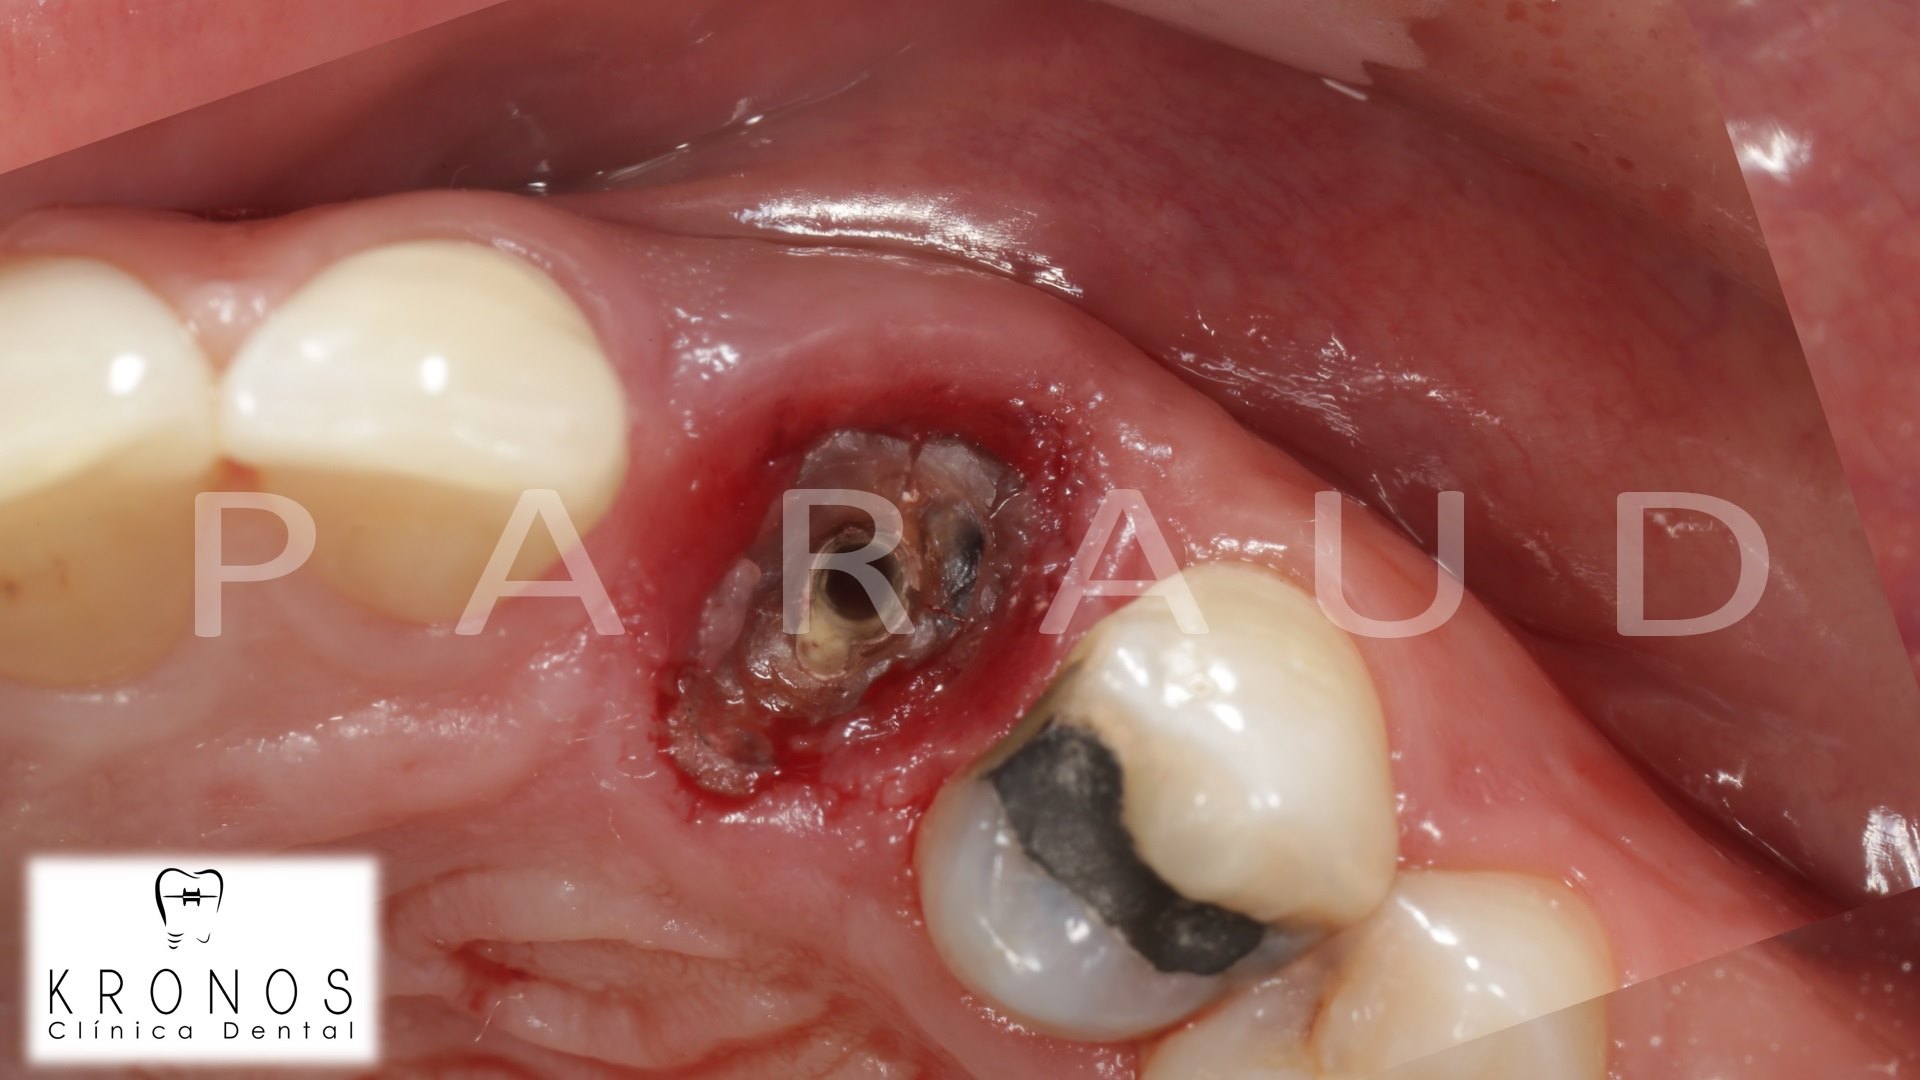

Clinical case: AnyRidge immediate loading

- Courtesy of Dr. Andres Paraud Freixas, Chile -

AnyRidge, ISQ value, initial stability, immediate loading, KnifeThread, maxillary anterior, Mega ISQ, Dr. Andres Paraud Freixas

AnyRidge implant system, Mega ISQ, Digital prosthesis

“Patient’s smile was recovered on the day of surgery

with reliable & highly-aesthetic results using AnyRidge & R2GATE. ”